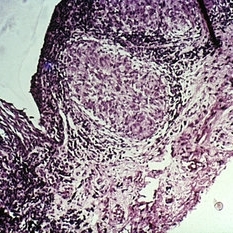

Slide 7-22

Feb 25 2019 by Lancaster Course in Ophthalmology

Squamous cell carcinoma of the conjunctiva with invasion into the substantia propria.

Condition/keywords: conjunctiva, substantia propia